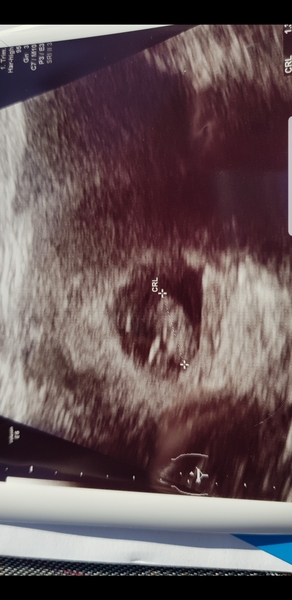

Hi all, sorry I went missing after asking about early scans!

I'm 7w6d today and we went for a scan. It was so quick but we saw the heart beat and it was definitely reassuring! Our little bean is 1.4cm and doing great ❤

Jenbot78 · 25/02/2019 21:07

Hi all I had a scan today too at 7+4 weeks. whowouldhavethoughtit nice to see the little heartbeat going like the clappers isn’t it?! Hematoma has shrunk too, so I’m pleased about that.

Catren · 25/02/2019 22:12

Thanks jenbot! Congrats on all the positive early scan results too.

We've just come from ours, and all is well! Raging heart beat and in the right spot, measuring 1cm and I'm 7+2. Eeeee!